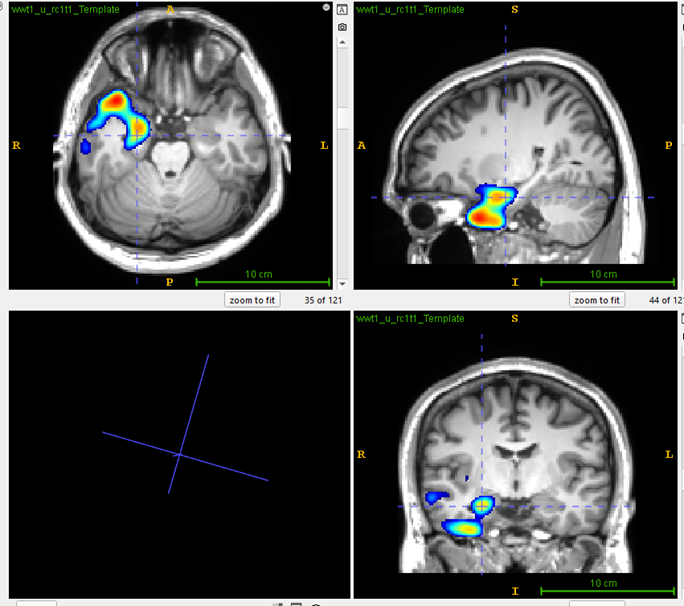

MRI Scan

Visual analysis: PET image of a drug-resistant frontal epilepsy patient, Hypometabolism not very focal and evident.

PASCOM: Focal hypometabolism was localized at the right inferior frontal lobe.